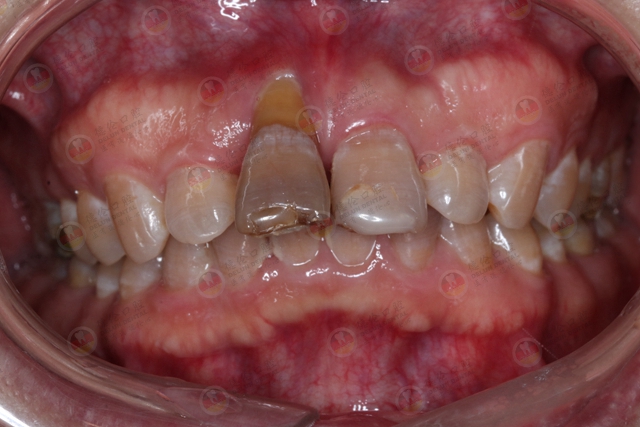

牙龈老是肿胀,牙齿底部也有黑色脏东西,而且牙根都暴露出来,好像是牙龈萎缩,给医生检查的时候,医生却告知牙龈内有牙结石,奇怪了,牙结石难道都不是长在牙齿表面吗?

它不光是长在牙龈上面那些我们肉眼能看到的地方,在牙龈下面看不到的地方也长有牙结石。

众所周知,牙结石在牙龈上面可以看到,也比较容易清洁。如果是在牙龈下,那就说明你有牙周炎了,一般牙周袋通常比较深,经常藏污纳垢,菌斑堆积后形成牙结石,造成牙龈周围有发黑现象!

牙龈下面的牙结石肉眼看不到,一般呈褐色或者黑色,附着更坚固,而且牙结石易吸附细菌/毒素,再加上本身对牙周组织的刺激,会使牙龈内侧溃疡,不易愈合,导致牙龈出血,牙周疾病加重,口臭,牙周袋,牙齿松动甚至脱落等。